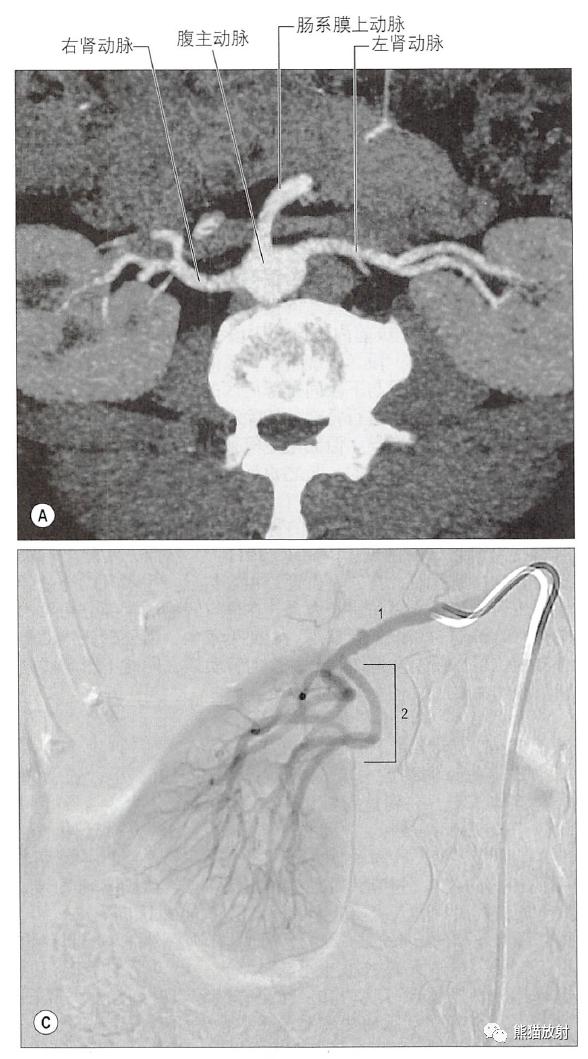

肾动脉CTA、肾动脉DSA、肾动脉分支数目和模式的变异

肾血管铸型

(肾动脉为红色,输尿管和肾盂、肾盏为黄色)